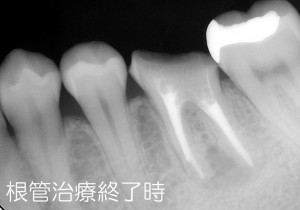

9年前ですので、まだまだマイクロスコープの取り扱いや根管治療の技術は未熟だったと思いますが、根管治療を行なう上で必須である「ラバーダム防湿」はしっかり行ない、治療を進めていきました。当時は、根管内が細菌感染でこんなに汚れているものなのかと衝撃を受けたことを思い出します。

そんなこんなで、えんや~こら~とがんばって、今とは使用している器材も違いますが、治療完了までこぎつけました。

その後は、土台と仮歯を入れて3ヶ月ほど経過観察をして、問題ないことを確認して最終的なかぶせ物を入れました。